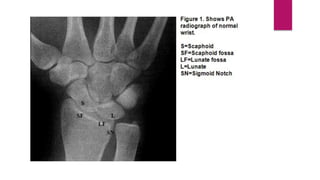

Anatomy

• Scaphoid and lunate fossa

• Ridge normally exists between these

two

• Sigmoid notch

• Second important articular surface

• Triangular fibrocartilage complex

(TFCC)

• Distal edge of radial to base of ulnar

styloid

Anatomy • Scaphoid andlunate fossa • Ridge normally exists between these two • Sigmoid notch • Second important articular surface • Triangular fibrocartilage complex (TFCC) • Distal edge of radial to base of ulnar styloid